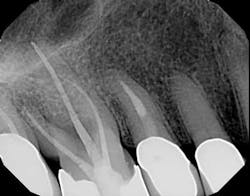

I then employ two instruments—the 30/02 Shaper and the 30/04 Finisher (Tango-Endo, EDS) that are also used in a 30-degree to 45-degree reciprocating handpiece, but designed with a more efficient flute design—to remove tissue and shave dentin away in the longer bucco-lingual isthmuses that may be present. These instruments are also highly resistant to separation, but for caution I suggest limiting their use to three teeth. Generally, there is little need to instrument the canals with larger instruments. If, in fact, the canal is wider than the instrument mesio-distally, in the same way the instruments can broaden the preparation bucco-lingually. It will also accomplish this task in the mesio-distal plane. Once shaped to these dimensions, the canal is properly sealed flooding the canal with epoxy resin cement via a bidirectional spiral applicator and the placement of a single Tango-Endo gutta-percha point (figures 2-3), demonstrated in the before-and-after radiographs.